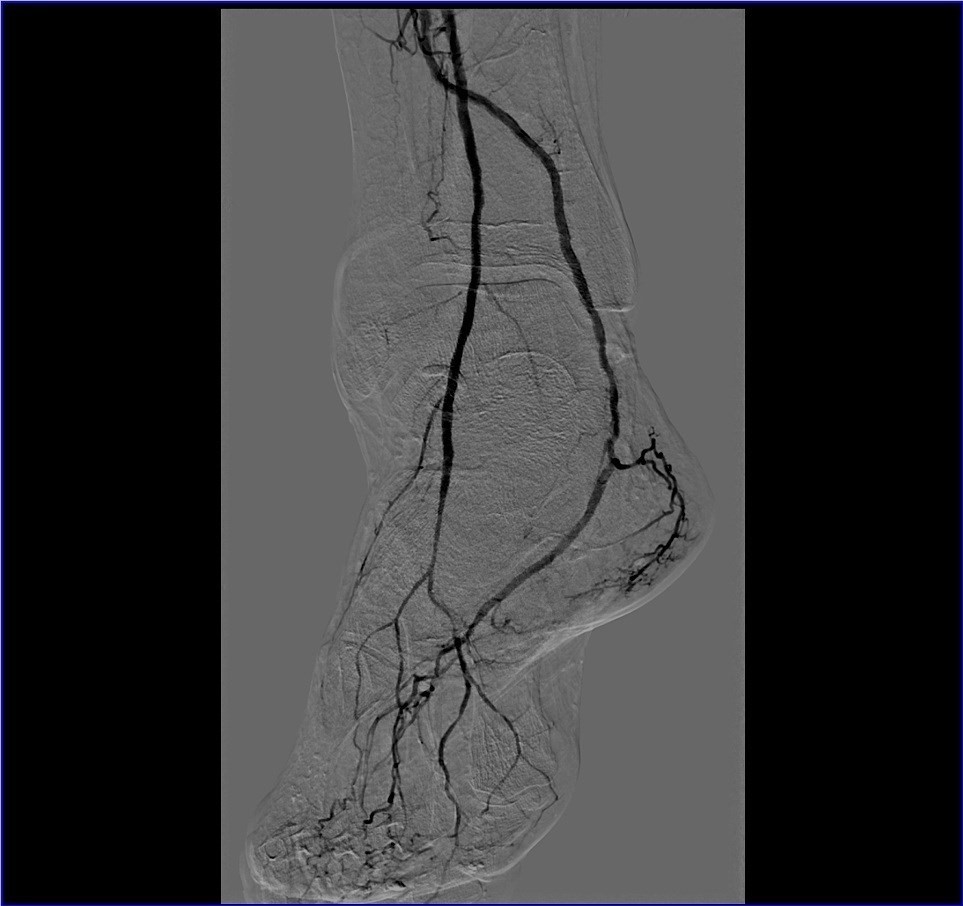

Ангиография артерий таза и нижних конечностей — метод визуализации просвета артерий путём введения в них через катетер рентгеноконтрастного вещества и одновременной рентгеноскопии (видеозаписи рентгеновской съемки), с фиксацией и обработкой полученного изображения на специальном оборудовании. При этом специалист получает объективную информацию об анатомическом строении сосудистого русла исследуемой области, скорости кровотока, наличии стенозов (сужений) и окклюзий (полной закупорки), степени развития коллатерального кровообращения в исследуемой конечности.

При выполнении ангиографии специалист получает объективную и точную информацию о строении и поражении артериального русла исследуемой области. Полученные изображения сохраняются в электронном виде и впоследствии могут быть записаны на диск и отданы на руки пациенту.